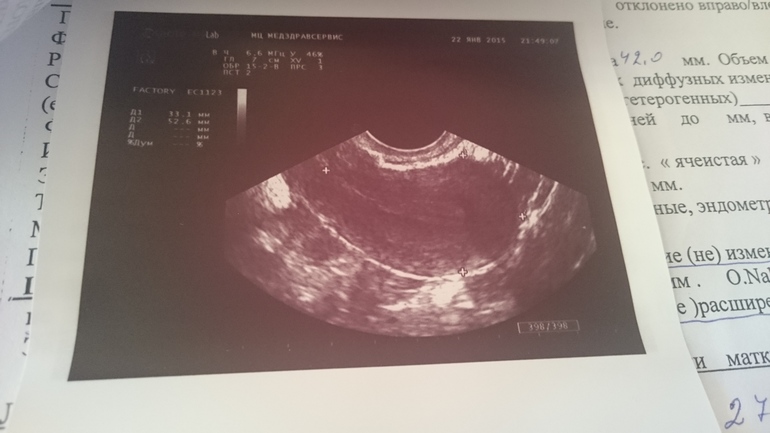

Но за весь этот месяц таки есть один положительный момент - эндик явно стал лучше, нет ячеистой структуры теперь))

Вот так, фото последнего УЗИ и анализов прилагаю)